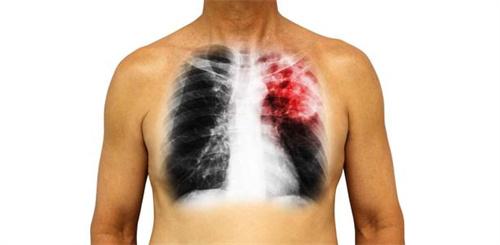

煙草中含有多種有害物質,包括一氧化碳,尼古丁,還有焦油等,這些有害物質長期不斷的刺激呼吸道,能夠使人的氣道粘膜發生慢性的炎癥性病變,氣道黏膜就會出現充血水腫,炎性物質滲出等現象,從而引起吸煙者出現慢性支氣管炎、慢性阻塞性肺氣腫還有可能會引起肺源性心臟病,肺癌等。

有一些人煙癮非常大,而且很難戒掉,這類人群的身體肯定已經受到了不同程度的危害,應該定期對身體做一些檢查,首先一定要保證每年都做一次常規的體檢,如果吸煙量較大的話,一般建議做體檢的時候增加肺功能檢查,如果本身就有不適的癥狀,可以做胸部CT檢查,還有肺功能和血常規檢查,因為鋅最容易造成肺部的疾病,還可能會引起支氣管炎,支氣管擴張,惡性腫瘤和支氣管肺癌等疾病。